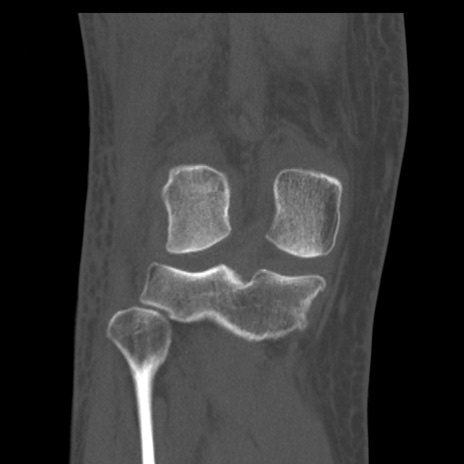

右膝関節CT

矢状断像